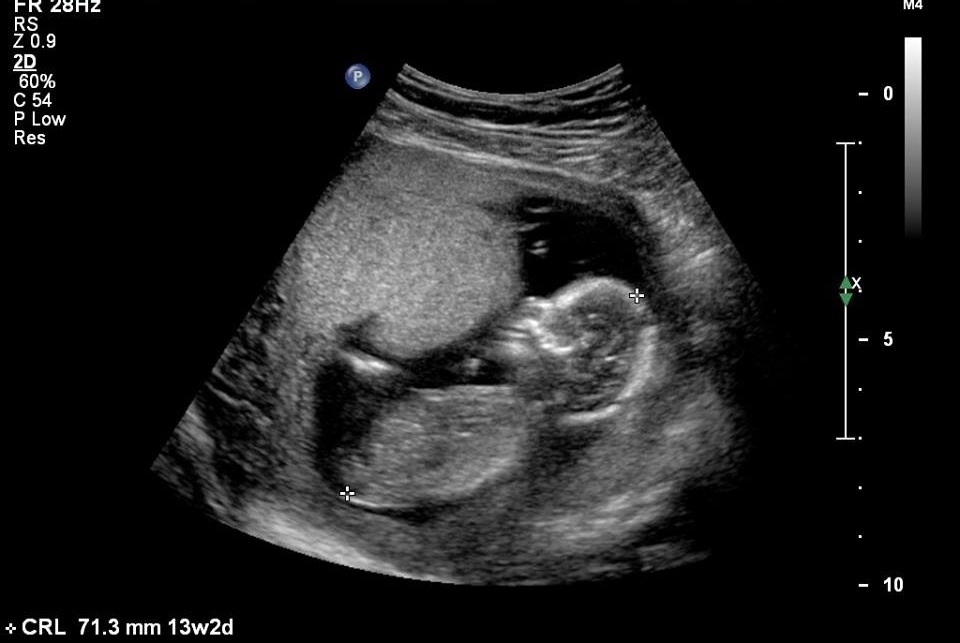

Here are my 14 week 5 day (my dates went back to normal dates) potty shots.. Tech did close up while doing scan and showed me baby had three lines and she thought it was a girl, and then said to not take that as a confirmed girl till 20 weeks!! What do you all think?